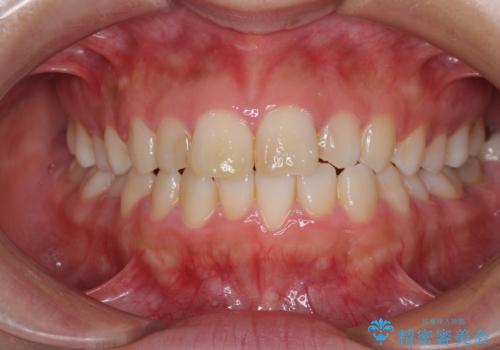

上顎の八重歯と下顎前歯の欠損 ワイヤー装置による抜歯矯正

八重歯で正中が右にずれている ワイヤー装置での抜歯矯正で正中位置を改善

担当医 藤巻太一朗